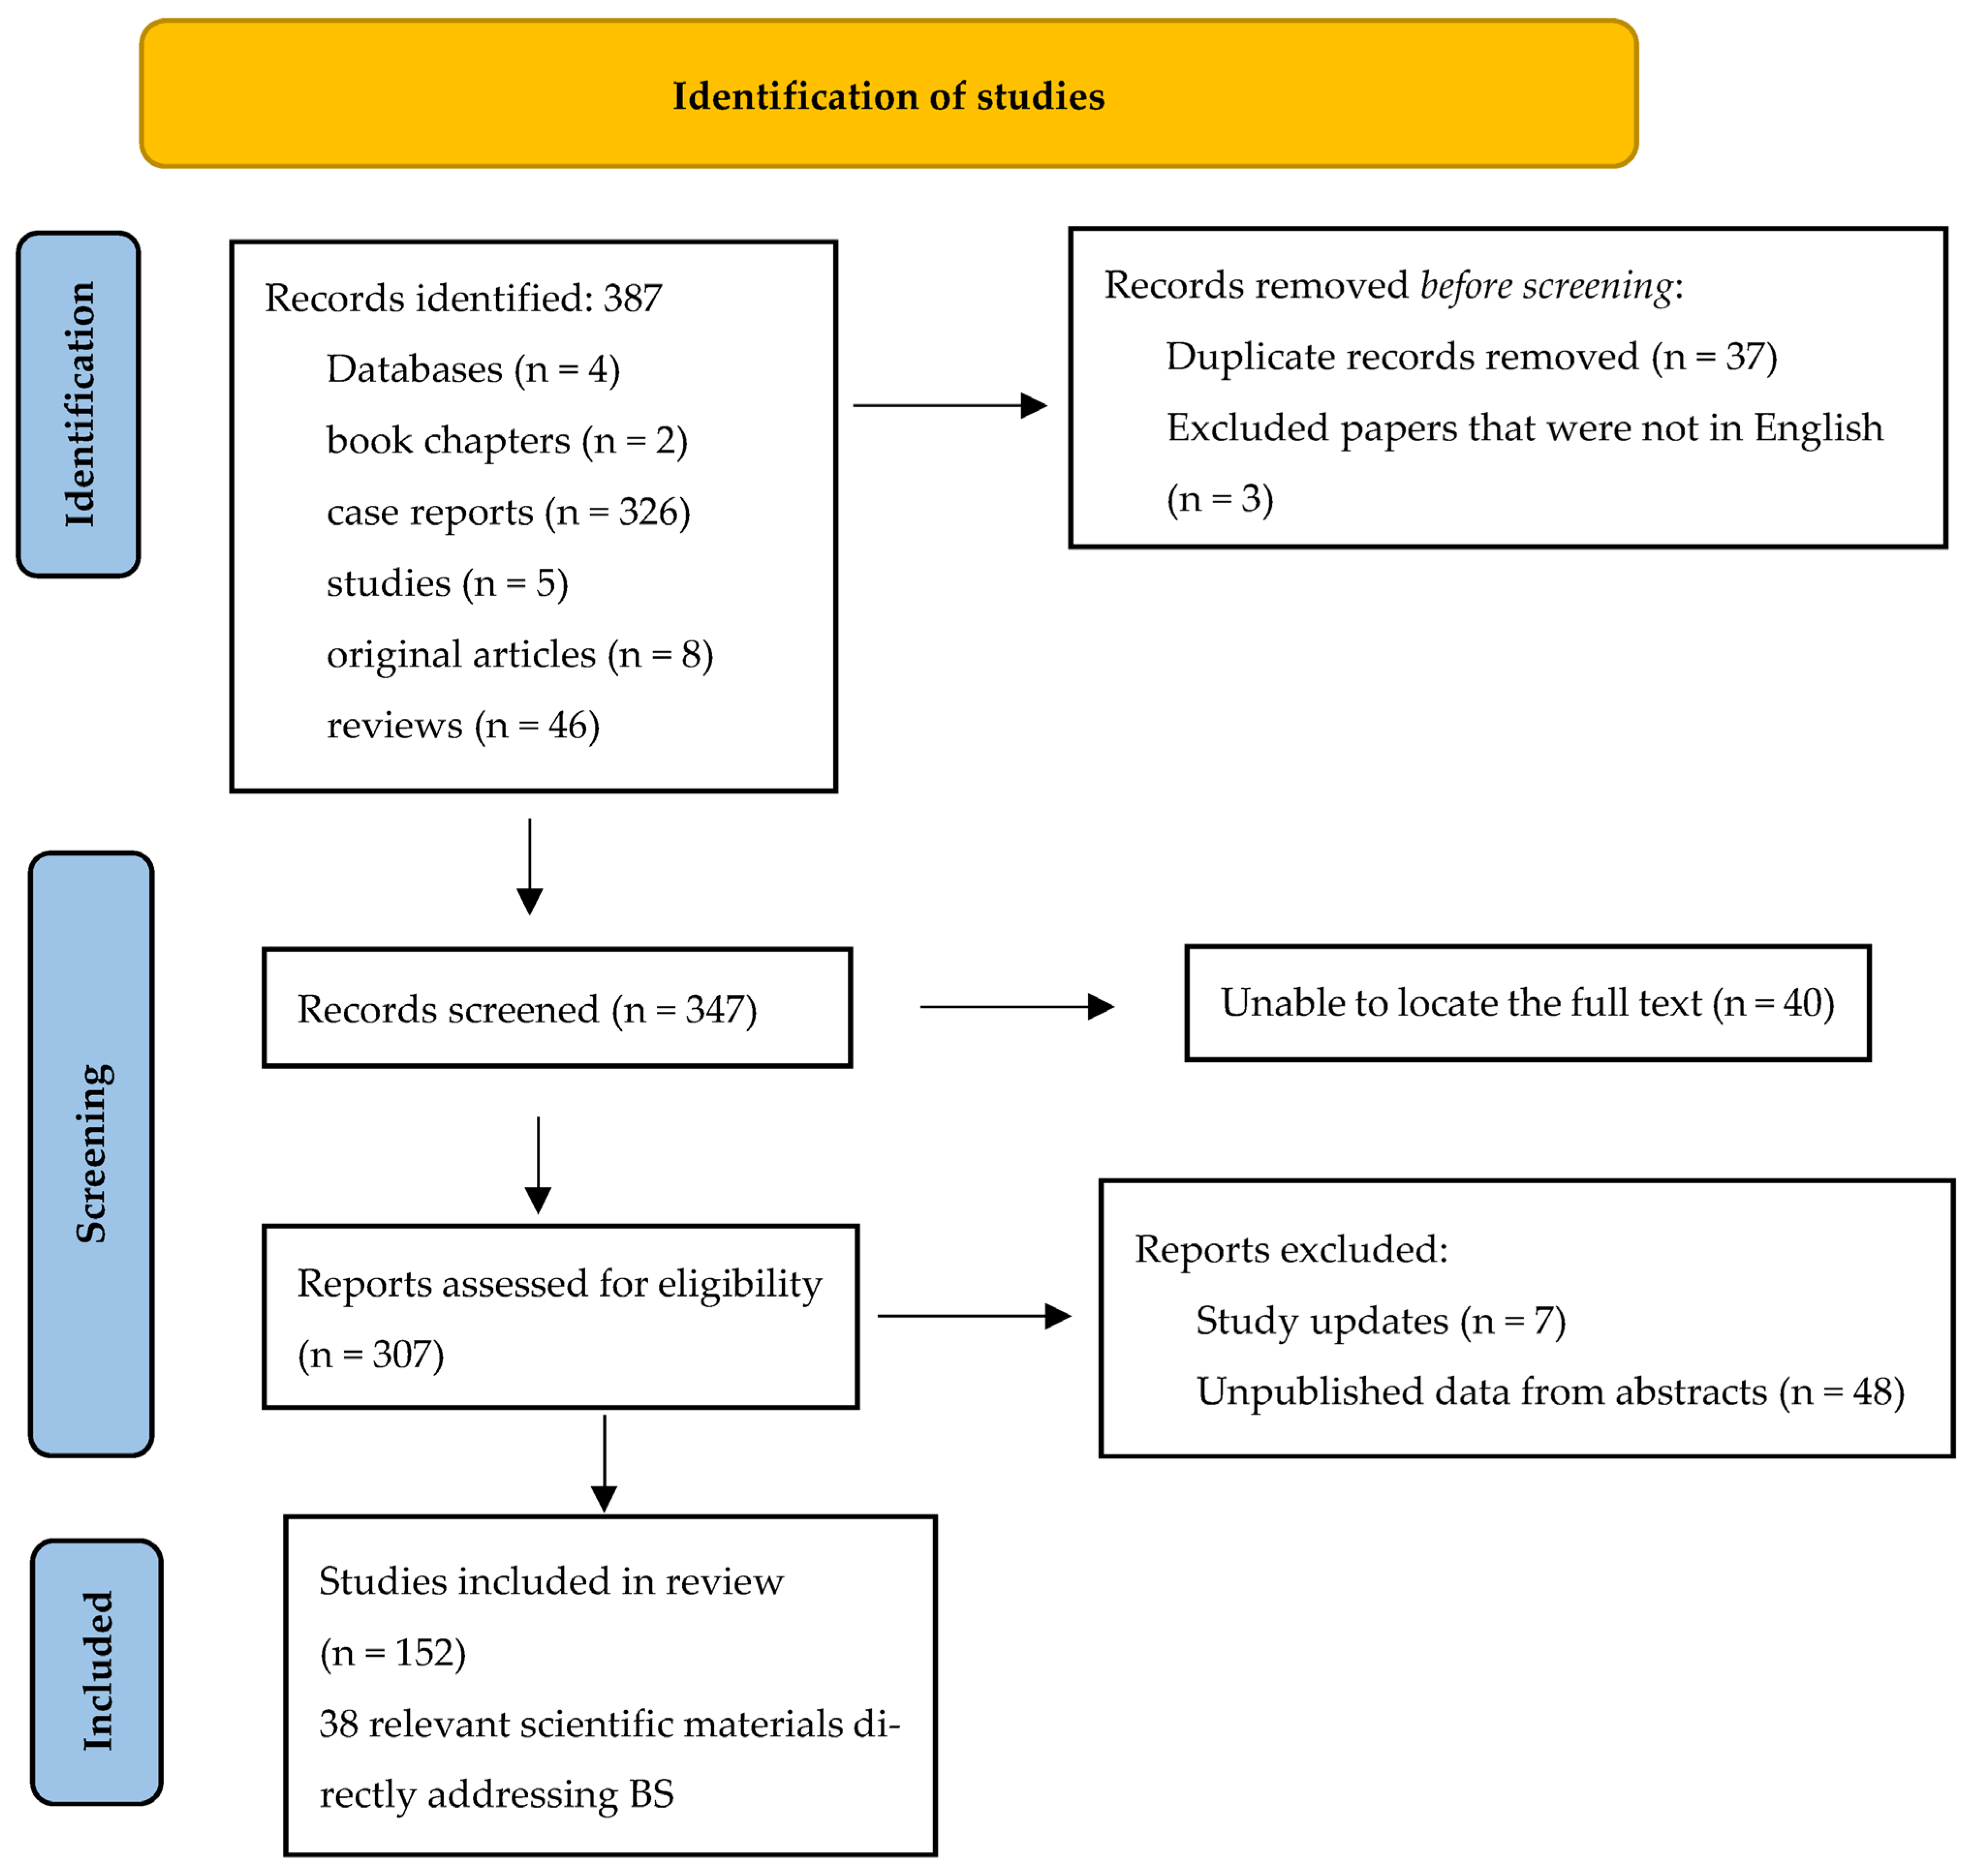

2. Objectives

3. Search Strategy